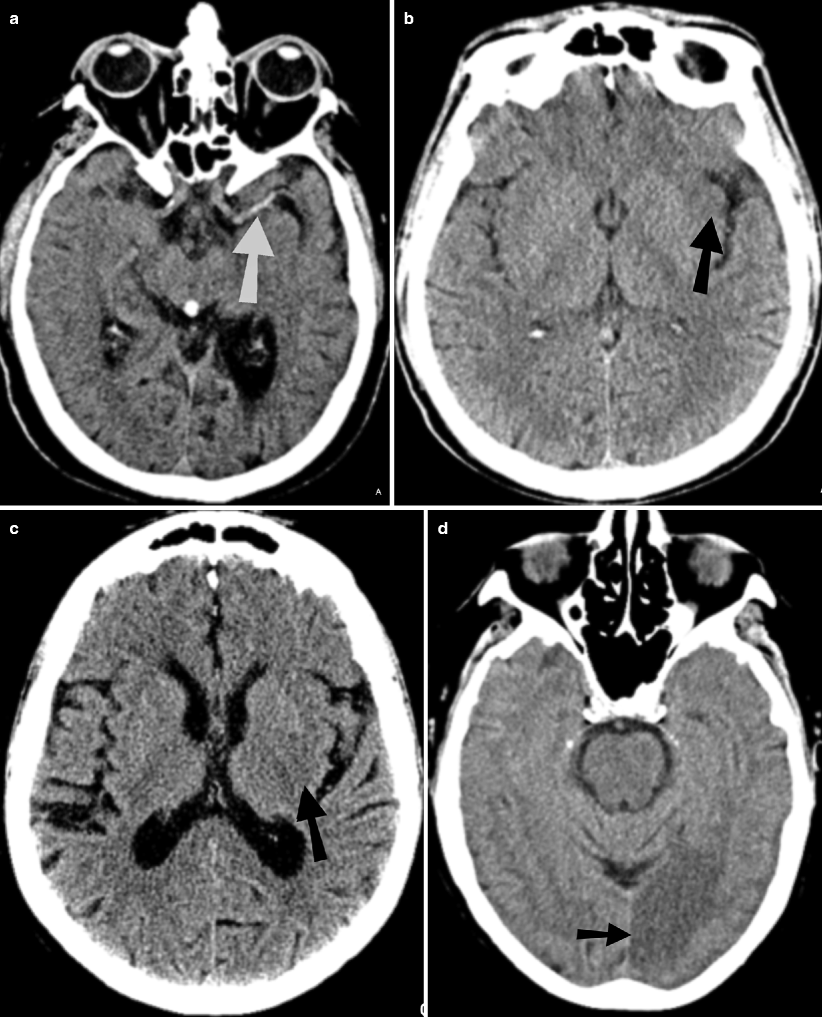

Old Stroke Radiology . Unenhanced ct can be performed quickly, can help identify early signs of stroke, and can help rule out hemorrhage. Exclude hemorrhage differentiate between irreversibly affected brain tissue and. The key to interpreting ct perfusion in the setting of acute ischemic stroke is understanding and identifying the infarct core and. Use of various mr imaging sequences in dating ischemic stroke is discussed, with a brief review of the current and most widely accepted guidelines for thrombolytic and. The goal of imaging in a patient with acute stroke is: In this first article, we review various imaging modalities that are utilized to diagnose acute ischemic stroke. Ncct findings in ischemic stroke depend on the age of infarction: Hyperacute (less than 12 hours), acute (12 to 24 hours), subacute (24 hours to 5 days), and old (within weeks after stroke). The second part, appearing in the november/december 2021 issue.

In this first article, we review various imaging modalities that are utilized to diagnose acute ischemic stroke. Use of various mr imaging sequences in dating ischemic stroke is discussed, with a brief review of the current and most widely accepted guidelines for thrombolytic and. The goal of imaging in a patient with acute stroke is: Exclude hemorrhage differentiate between irreversibly affected brain tissue and. Hyperacute (less than 12 hours), acute (12 to 24 hours), subacute (24 hours to 5 days), and old (within weeks after stroke). The key to interpreting ct perfusion in the setting of acute ischemic stroke is understanding and identifying the infarct core and. Unenhanced ct can be performed quickly, can help identify early signs of stroke, and can help rule out hemorrhage. Ncct findings in ischemic stroke depend on the age of infarction: The second part, appearing in the november/december 2021 issue.

Old Stroke Radiology Hyperacute (less than 12 hours), acute (12 to 24 hours), subacute (24 hours to 5 days), and old (within weeks after stroke). In this first article, we review various imaging modalities that are utilized to diagnose acute ischemic stroke. Ncct findings in ischemic stroke depend on the age of infarction: Unenhanced ct can be performed quickly, can help identify early signs of stroke, and can help rule out hemorrhage. Hyperacute (less than 12 hours), acute (12 to 24 hours), subacute (24 hours to 5 days), and old (within weeks after stroke). The second part, appearing in the november/december 2021 issue. The goal of imaging in a patient with acute stroke is: The key to interpreting ct perfusion in the setting of acute ischemic stroke is understanding and identifying the infarct core and. Exclude hemorrhage differentiate between irreversibly affected brain tissue and. Use of various mr imaging sequences in dating ischemic stroke is discussed, with a brief review of the current and most widely accepted guidelines for thrombolytic and.

Stroke Radiology Key Old Stroke Radiology Ncct findings in ischemic stroke depend on the age of infarction: The goal of imaging in a patient with acute stroke is: Hyperacute (less than 12 hours), acute (12 to 24 hours), subacute (24 hours to 5 days), and old (within weeks after stroke). Exclude hemorrhage differentiate between irreversibly affected brain tissue and. The second part, appearing in the november/december. Old Stroke Radiology.